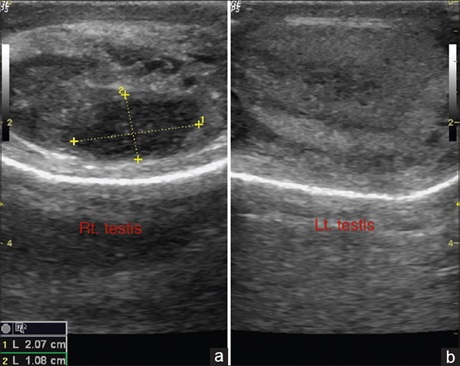

genitourinary system being the most common affected site. We present a classical case of tuberculous epididymo-orchitis with

clinical, sonographic and histopathological (macro and microscopic) findings as well as the precise management plan incorporated.

The sonographic imaging overlap with bacterial epididymo‑orchitis, malignant testicular lesions and testicular torsion is discussed.